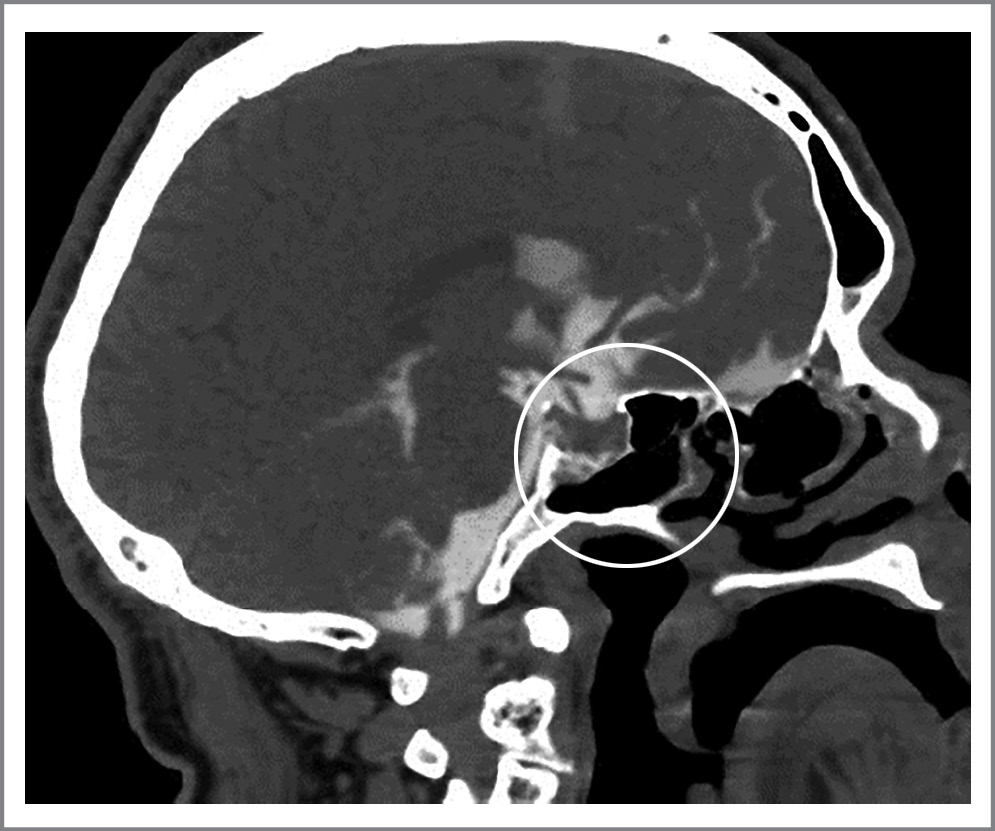

Перед операцией проведена КТ-цистернография, которая выявила наличие дефекта основания черепа: в области турецкого седла (рис. 3).

Рис. 3. КТ-цистернография. Фронтальная проекция. Дефект в области турецкого седла.